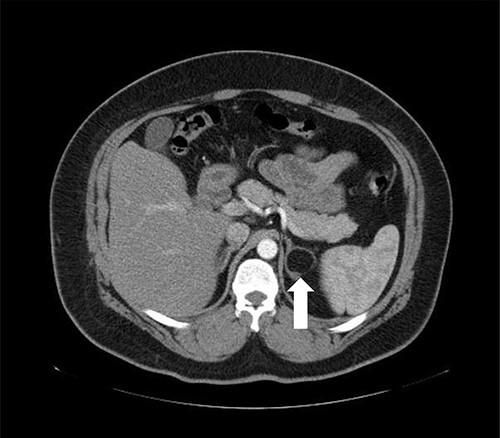

Patient 1 is a 45-year-old male, who came to our private clinic complaining of obesity with a body mass index (BMI) of 41 kg/m2. His other comorbidities included hypertension (HTN) controlled on one anti-HTN medication and diabetes mellitus (DM) on oral hypoglycemic agents (OHA). He denied any symptoms of reflux or any family history of adrenal/thyroid/parathyroid diseases. He was discovered to have a 4 cm right adrenal incidentaloma on a contrast-enhanced computed tomography (CECT) of the abdomen as a workup for abdominal pain (Fig. 1). Preoperative preparation included obesity workup with complete blood count, coagulation profile and a chest X-ray. Endocrine workup included a screening for possible functional incidentaloma, with adrenocorticotropic hormone of 2.8 pmol/l, aldosterone/renin ratio (ARR) of 1.7 ng/dl per ng/(ml·h), serum metanephrine of 343 pg/ml (reference <90), serum normetanephrine of 401 pg/ml (reference <129) and a normal serum morning cortisol of 168 nmol/l (reference 101–535). A diagnosis of right adrenal pheochromocytoma was established. A cardiac consultation was done and determined that the patient is fit for surgery and formulated a preoperative medication with α- and β-blockers.

Axial CT of the abdomen showing the right adrenal mass in Patient 1 (white arrow).